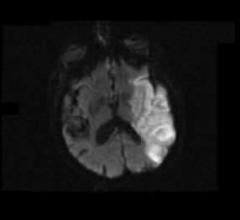

July 29, 2011 — Oxygen Biotherapeutics Inc. and privately held Aurum Biosciences Ltd. of Glasgow, Scotland, have signed a letter of intent (LOI) to conduct preclinical research for imaging and therapeutic intervention of acute ischemic stroke. Aurum, using Oxygen’s proprietary Oxycyte PFC (perfluorocarbon) emulsion in combination with Aurum’s proprietary Glasgow Oxygen Level Dependent (GOLD) magnetic resonance imaging (MRI) techniques, will conduct the research.